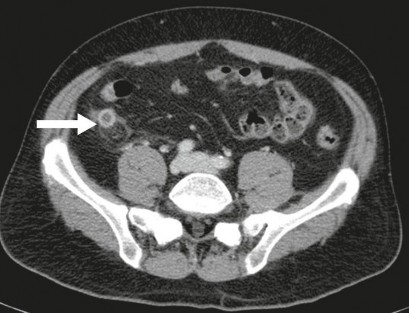

Thì tĩnh mạch trong quá trình tiêm thuốc cản quang (khoảng 110 giây sau khi tiêm 130ml thuốc cản quang vào tĩnh mạch) rất thích hợp để chẩn đoán viêm ruột thừa vì các dấu hiệu viêm ruột thừa ở thời điểm này có thể được đánh giá một cách tốt nhất. Ngoài các tiêu chuẩn trên của CLVT không tiêm thuốc, hình ảnh trên CLVT có tiêm thuốc cản quang cho thấy ruột thừa dày thành và tăng tỷ trọng hình vòng. Đây là một yếu tố để chẩn đoán. Một ưu điểm nữa là có thể hình dung chính xác các biến chứng. Do đó, ví dụ như trong trường hợp thủng ruột thừa, một ổ áp xe cản quang ở vùng hố chậu phải có thể được đánh giá tốt hơn so với CLVT không cản quang [35].

Hình 1.6: CLVT có tiêm thuốc cản quang trên bệnh nhân VRTC [35]